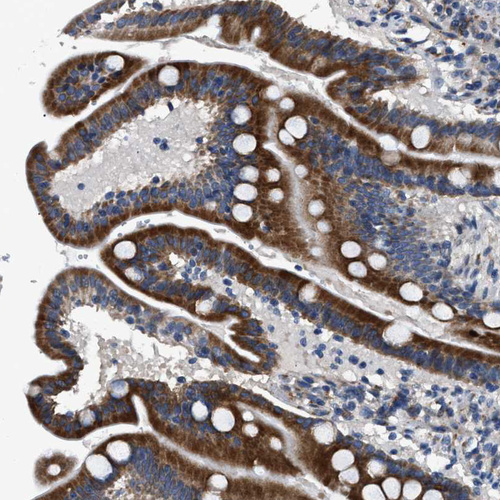

Immunohistochemical staining of human placenta shows strong cytoplasmic positivity in trophoblastic cells.